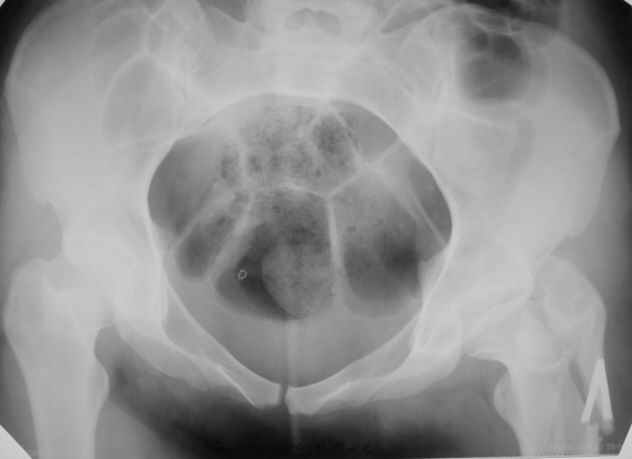

Пациентка 23 лет, доставлена в клинику с Диагнозом: Закрытый сегментарный оскольчатый перелом левой бедренной кости в верхней и средней трети. Травма в результате ДТП 10.03.2006г. Из анамнеза у пациентки диспластический левосторонний коксартроз, S-образный сколиоз 2ст. В 1999г в Кургане выполнялась остеотомия бедра в нижней трети и коррекция укорочения конечности на 3 см (рентгенограммы бедра и таза до травмы в приложении). До получения травмы пациентка ходила без боли с полной нагрузкой на левую ногу. Учитывая дисплазию левого ТБС, пациентке, вероятно, предстоит операция тотального эндопротезирования лев ТБС, что требует анатомичного восстановления проксимальногоотдела бедра. Рассматриваются следующие вариант остеосинтеза:1) Экстракортикальный остеосинтез проксимального и дистального перелома пластиной с угловой стабильностью типа LISS( г Рыбинск); 2) Ретроградный интрамедуллярный блокированный остеосинтез дистального перелома и накостный синтез проксимального пластиной с угловойстабильностью; 3) Остеосинтез бедра в аппарате внешней фиксации с фиксацией таза и возможной открытой адаптацией фрагментов. Хотелось бы узнать Ваше мнение. С уважением Украинский Евгений, г.Краснодар, ККБ N1, ТОО N3.

Не во всех случаях, особенно у молодых!, при дисплазии ТБС требуется эндопротезирование. По представленным снимкам четко видны хорошо сохраненный тазобедренный сустав и тем более больная до травмы не имела симптомов диспластического сустава. В будущем при появлении симптомов, можно попытаться сделать реконструктивную работу по сохранению сустава: ПАО с удлинением шейки (аналогичные случаи были

рассмотрены форумом)